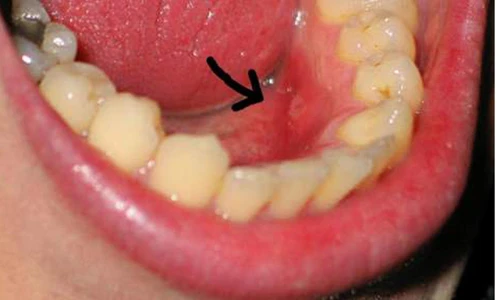

Đi tìm dấu vết khối u. Những khối u này đôi khi không hề mang lại cảm giác đau đớn cho khổ chủ. Chính vì vậy, bạn cần phải đặc biệt chú trọng đến các dấu hiệu như khối u lồi lên với màu nhạt hoặc trắng.

Khi dùng tay kiểm tra, khối u thường được bao quanh bởi một vành cứng. Ngoài ra, nó cũng dễ dàng được nhận diện bởi sự gia tăng về kích cỡ theo thời gian.